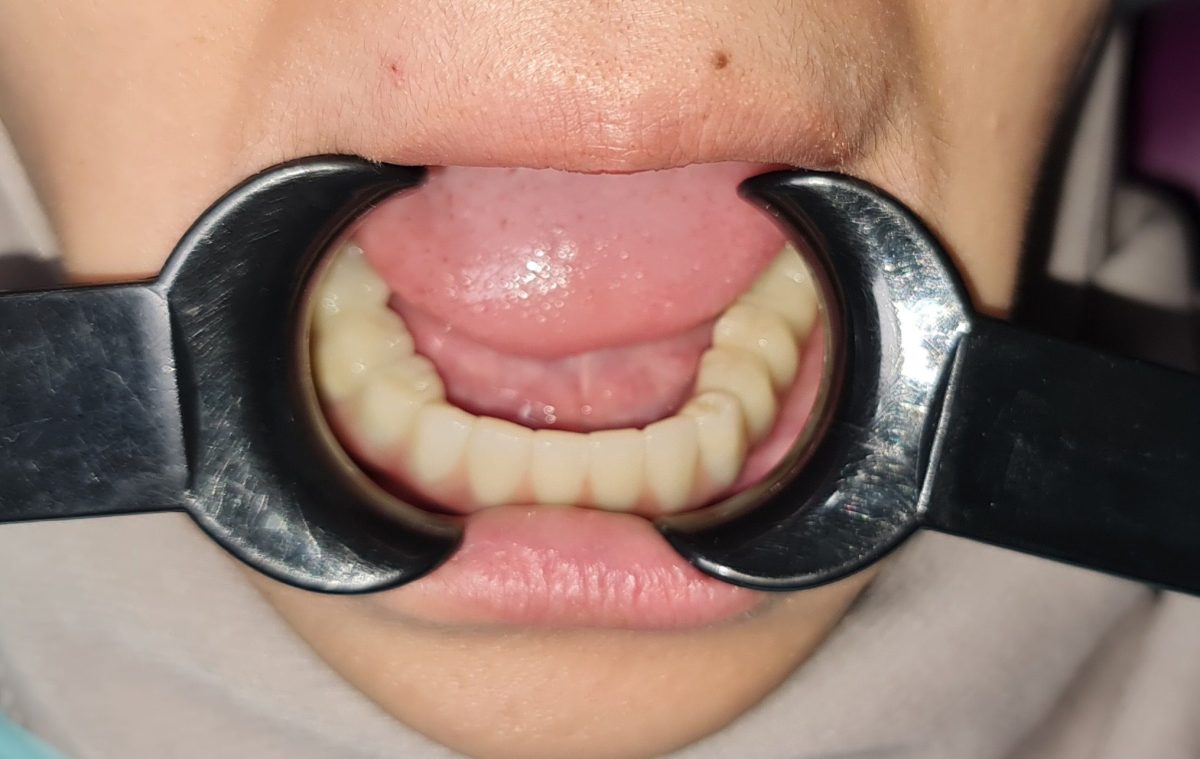

All-on-X dental implants are a full-arch restoration solution designed for patients with multiple missing, damaged, or failing teeth. The treatment uses four, five, or six dental implants to support a fixed full-arch prosthesis, restoring both function and aesthetics.

The final full-arch prosthesis is fabricated and fitted over several appointments to optimize comfort, bite, and aesthetics.

Full mouth rehabilitation is a comprehensive dental treatment designed to restore both function and aesthetics for patients with severely worn, damaged, missing, or failing teeth.

Our dentists focus on creating natural-looking smiles that balance aesthetics, comfort, and long-term function.